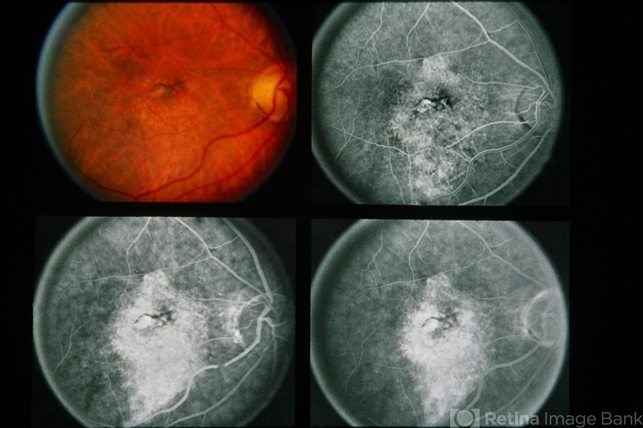

- subretinal neovascularization (SRNV)

- 75-year-old white female. SRNV-MD. RE 8/200 LE 20/25.